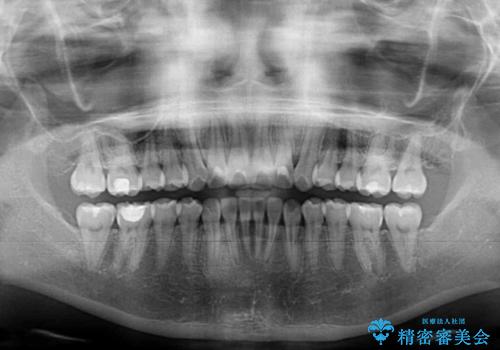

毎日しっかりと装着してくださったので、概ねシミュレーション通りに歯を移動させることができました。

治療前には接触することのなかった上下の前歯が接触するようになり、食事の際前歯でものをかみ切れるようになりました。

気にしていた口元の印象が改善され、患者様には大変満足していただきました。